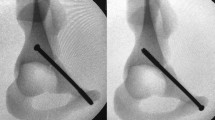

For biomechanical tests, research groups could choose between human cadaveric pelves prepared in various ways, or synthetic pelvis models, which consisted of bone substitutes intended to reflect the biomechanics of physiological bone. Most research groups investigating fixation methods for acetabular fractures used synthetic pelves models (25 test setups) [28,29,30,31,32, 35,36,37,38,39,40,41,42,43,44, 49,50,51, 54,55,56, 60,61,62,63]. These models consisted of a whole pelvis or a hemipelvis model fixed in different ways to enable particular loading directions. Only 32% (12 test setups) of the pelvis models were human cadaveric pelves [33, 34, 44,45,46,47,48, 52, 53, 57,58,59]. One study even used a synthetic as well as a cadaveric pelvis model [44]. Cadaveric pelves and synthetic pelves were used about equally often for testing posterior wall fractures (synthetic models: 4; cadaveric models: 5), but in other fracture types synthetic pelvis models were used more frequently. Abnormalities of the cadaveric pelvis were ruled out by radiography, DXA and/or CT scan. The human pelves were prepared in different ways, either by removing the femur and loading with an artificial femoral head or by maintaining both proximal femora and embedding them for double-limb stance loading. Furthermore, soft tissues, such as ligaments of the SI-joint or hip joint capsule, were removed to a variable extent in the different publications.

A simple single-leg stance loading direction was used in 7 of 36 biomechanical test setups and consisted of an anatomical femoral hip prosthesis, which was mounted with the shaft and moveably connected with the pelvis model in a single-leg stance position, usually with 15° anteversion [28, 35, 36, 39, 42, 55, 62]. The loading force was applied via defined parts (e.g. SI-joint or sacrum) of the (hemi-)pelvis model. Culemann et al. established a modified single-leg stance model with a mobile pelvis, which was fixed on the head of a hip prosthesis with cord units simulating the pull forces of the hip abductor muscles. The axial compressive load was applied through the first sacral vertebra via a ball joint. This allows the pelvis to move in all three planes [44]. Comparable models of a modified single-leg stance protocol were applied in a total of four biomechanical tests [44, 50, 51].

In one commonly used loading protocol, the loading force was applied with an artificial femoral head (without a simulated CCD angle of an anatomical femoral hip prosthesis) in a mediosuperior direction of approximately 45° mediosuperiorly and 15° to 25° posteriorly (12 biomechanical test setups) [29,30,31,32, 34, 37, 38, 41, 49, 53, 63]. Such a loading direction was frequently used for the evaluation of transverse fractures and ACPHT fractures. The model of a mediosuperior loading direction was based on observations of Bergman et al., who evaluated hip joint loading during daily activities by implanting telemetering total hip prosthesis in patients undergoing THA. They observed that the main loading force on the acetabulum during the stance runs along the axis of the femoral neck with a mediosuperior angle of 45° [72,73,74]. Mehin et al. applied the loading force with an artificial femoral head perpendicularly to the acetabulum, in order to provoke movements at the fracture sites [33]. This loading perpendicular to the acetabulum was found in four biomechanical test setups [33, 43, 46, 47].